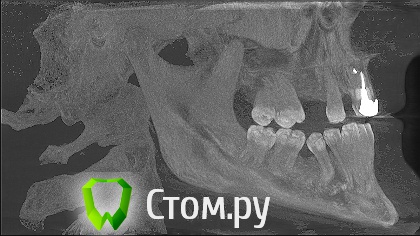

sergey765 Опубликовано 11 июня, 2014 Автор Поделиться Опубликовано 11 июня, 2014 посмотрите пожалуйста КТ. Ссылка на комментарий

sergey765 Опубликовано 11 июня, 2014 Автор Поделиться Опубликовано 11 июня, 2014 могу вам ещё снимков выложить.их довига. беспокаят меня боли после удаления .прошло 5 недель. снимки девушка лет 20 эти смотрела. сказала что у меня там инфекции дофига. типа давай я тебя на понедельник к хирургу запишу. он ранку вскроет. прочистит Ссылка на комментарий

Bier Опубликовано 11 июня, 2014 Поделиться Опубликовано 11 июня, 2014 это все не информативные кадры, в прикрепленных темах есть инструкция, выкладывайте КТ целиком, наш рентгенолог скачает и выложит срезы. 3 Ссылка на комментарий

sergey765 Опубликовано 12 июня, 2014 Автор Поделиться Опубликовано 12 июня, 2014 (изменено) ещё хочу добавить. когда у меня удаляли 5 недель назад мой зуб. из лунки выскочил какой-то кусок черного мяса размером почти с горошину. это не кровяной сгусток а именно кусок застывшиго черного мяса. крови почти не было. так во этот кусок мяса залез обратно в десну-челюсть только дня через 4. и видна в лунке была только челюсть желтого цвета и посередине дырка из кости куда этот кусок мяса залез. потом я пришел к врачу который удалял она мне на кость положила лекарство желтого цвета которое тупо застыло и не растворялось. стало как камень. от запаха этого лекарства я реально чуть не сдох. так было ещё дней 5. потом лунка затянулась но кусок желтой кости торчит досихпор. еще при удалении пол левой челюсти побелело. образовался какой-то белый налет на левой половине верхней и нижней десне. через 2-3 дня после удаления я провел пальцем по деснам и этот налет с десны снялся но остался белый комок на пальце которым я проводил по десне... еще у меня постоянно уже года 2 наверно из левого глаза идет временами гной... посмотрите на снимке там даже с левой стороны челюсти (правой снимка) есть какое-то черное пятно. Изменено 12 июня, 2014 пользователем sergey765 Ссылка на комментарий